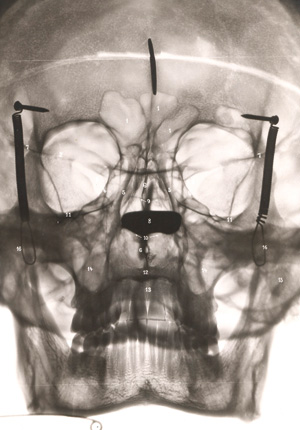

Kuttner, Arthur

Die entzündlichen Nebenhöhlenerkrankungen der Nase im Röntgenbild

Zuschlag

800€ (US$ 909)